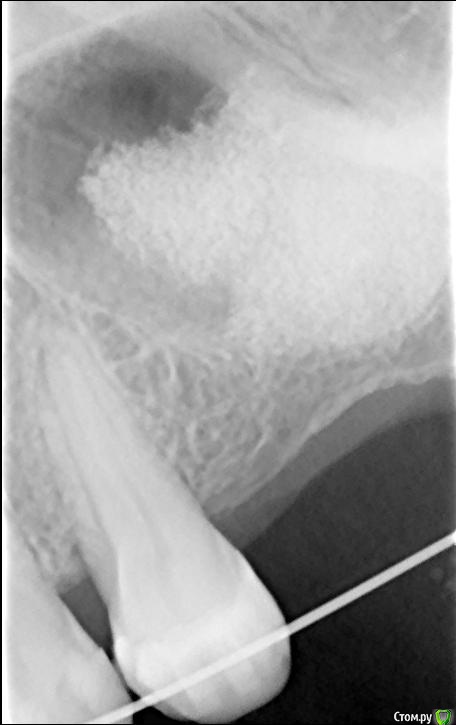

shilka Опубликовано 10 января, 2018 Поделиться Опубликовано 10 января, 2018 Добрый день коллеги! Нужен совет. Пациентка делала синус-лифт в другой клинике, но имеет желание поставить имплант у меня. 6 месяцев после лифта прошли,но глядя на снимок меня обуревают некоторые сомнения. Ссылка на комментарий

Bysh Опубликовано 10 января, 2018 Поделиться Опубликовано 10 января, 2018 КТ бы, а то прицельный мало информативен 1 Ссылка на комментарий

shilka Опубликовано 10 января, 2018 Автор Поделиться Опубликовано 10 января, 2018 КТ бы, а то прицельный мало информативенда думаю тоже сделать.Но вообще напрягает узкая бухта, есть вероятность синусита Ссылка на комментарий

shilka Опубликовано 12 января, 2018 Автор Поделиться Опубликовано 12 января, 2018 Кто советует и зачем?тут просто инсталлировать имплант и всё....может десны добавить В анамнезе после этого лифта был синусит, так как другой клинике делали,не хочется быть-"кто последний тот и папа"))). И проекция установки импланта такая,что в бухту имплант попадает,ближе к 7ке если только ставить. КТ постараюсь сделать,выложу Ссылка на комментарий

Bier Опубликовано 15 марта, 2019 Поделиться Опубликовано 15 марта, 2019 Что за гадание на кофейной гуще? Это даже не орто, прицельный снимок! Что вы хотите на нем увидеть? Делайте КТ и будем обсуждать! Ссылка на комментарий